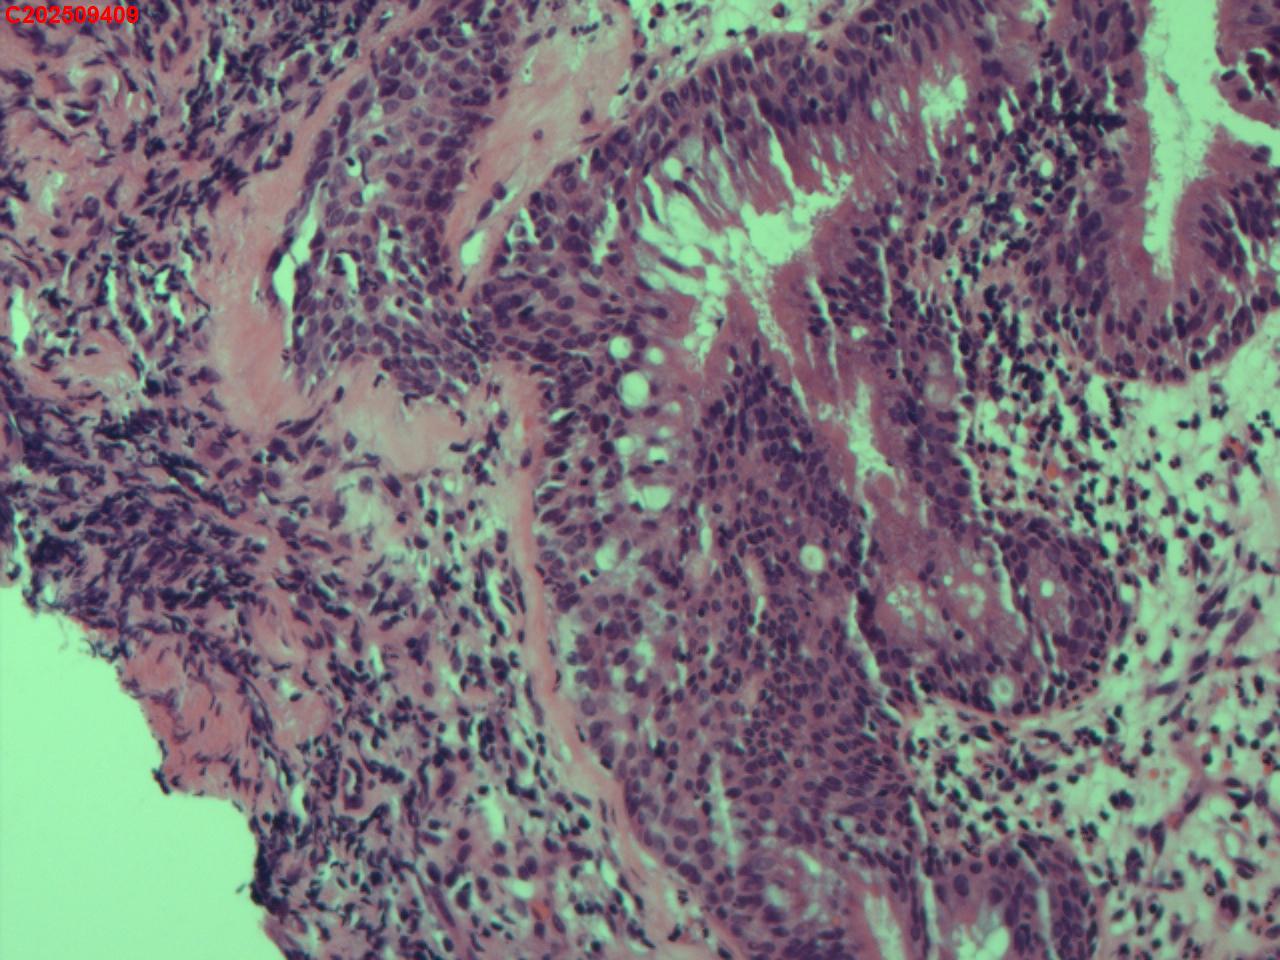

性别年龄62岁临床诊断社区获得性肺炎,肺占位性病变带除外

一般病史胸部CT:双肺可见多发斑片状、结节状高密度影,右肺上叶及左肺下叶病灶内见多发空洞,右侧少量胸腔积液。

标本名称纤支镜咬检

大体所见纤支镜:气管通畅,隆突锐利。右肺主支气管通畅,右肺上叶见少量痰液,负压吸引后见上叶开口干酪坏死物质附着,上叶各段级支气管通畅未见新生物及坏死物质,中叶、下叶背段支气管通畅,下叶基底段见新生物阻塞气道,粘膜无充血。左肺主支气管、上叶、下叶及各段级支气管通畅,粘膜无充血,未见新生物及坏死物。

考虑:支气管炎性息肉